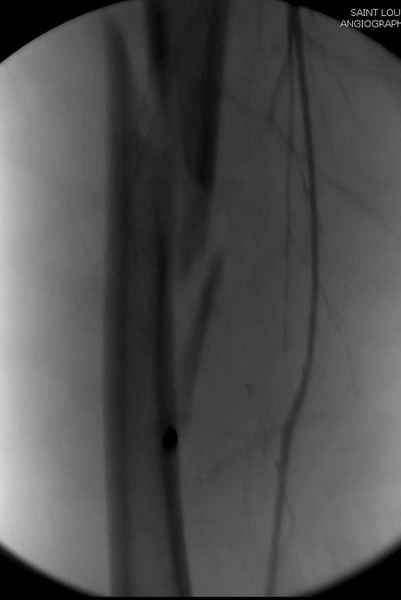

Как раз недавно у меня был примерный случай: больному 36 лет, поступил ночью, травма в результате мотоциклетной аварии, кроме чрезвертельного и спирального перелома левого бедра имеется переломы костей предплечья с этой же стороны. Скелетное вытяжение, а на следующий день больной про оперирован на ортопедическом столе с дистракцией. Чтобы не расколоть чрезвертельный перелом провели временную спицу ближе к переднему кортексу, из малого разреза костодержатель для репозиции, а фиксацию провели антиградным штифтом. Этапы операции на снимках.

Второй случай тоже репозиция из малого доступа, больному 19 лет, множественные огнестрельные повреждениия конечностей, живота и черепа, правая конечность холодная, без пульсации. Ортопедический диагноз: огнестрельный перелом правого бедра. При срочной ангиографии повреждения сосудов не подтвердилось, конечность из-за ургентности состояния больного зафиксирована временным наружным фиксатором и больной оставлен на операционном столе для срочной лапаротомии хирургической службой.

Больной долго оставался нестабильным, только на 14 день удалось заменить на антеградный интромедуллярный штифт TFN (trochanteric femoral nail) SmithNephew. После неудачной попытки закрытой репозиции, несмотря на использование "joystick", проксимальный стержень от

наружного фиксатора, (перелом начал срастаться) репозицию провели из малого доступа, затем остальные этапы операции.

Случай был представлен из-за того, что больного оперировали после наружной фиксации и был риск инфекцирования через места проведения стержней (на снимках), прошло больше 3 месяцев, выписан из амбулаторной службы из-за отсутсвия надобности дальнейшего наблюдения.